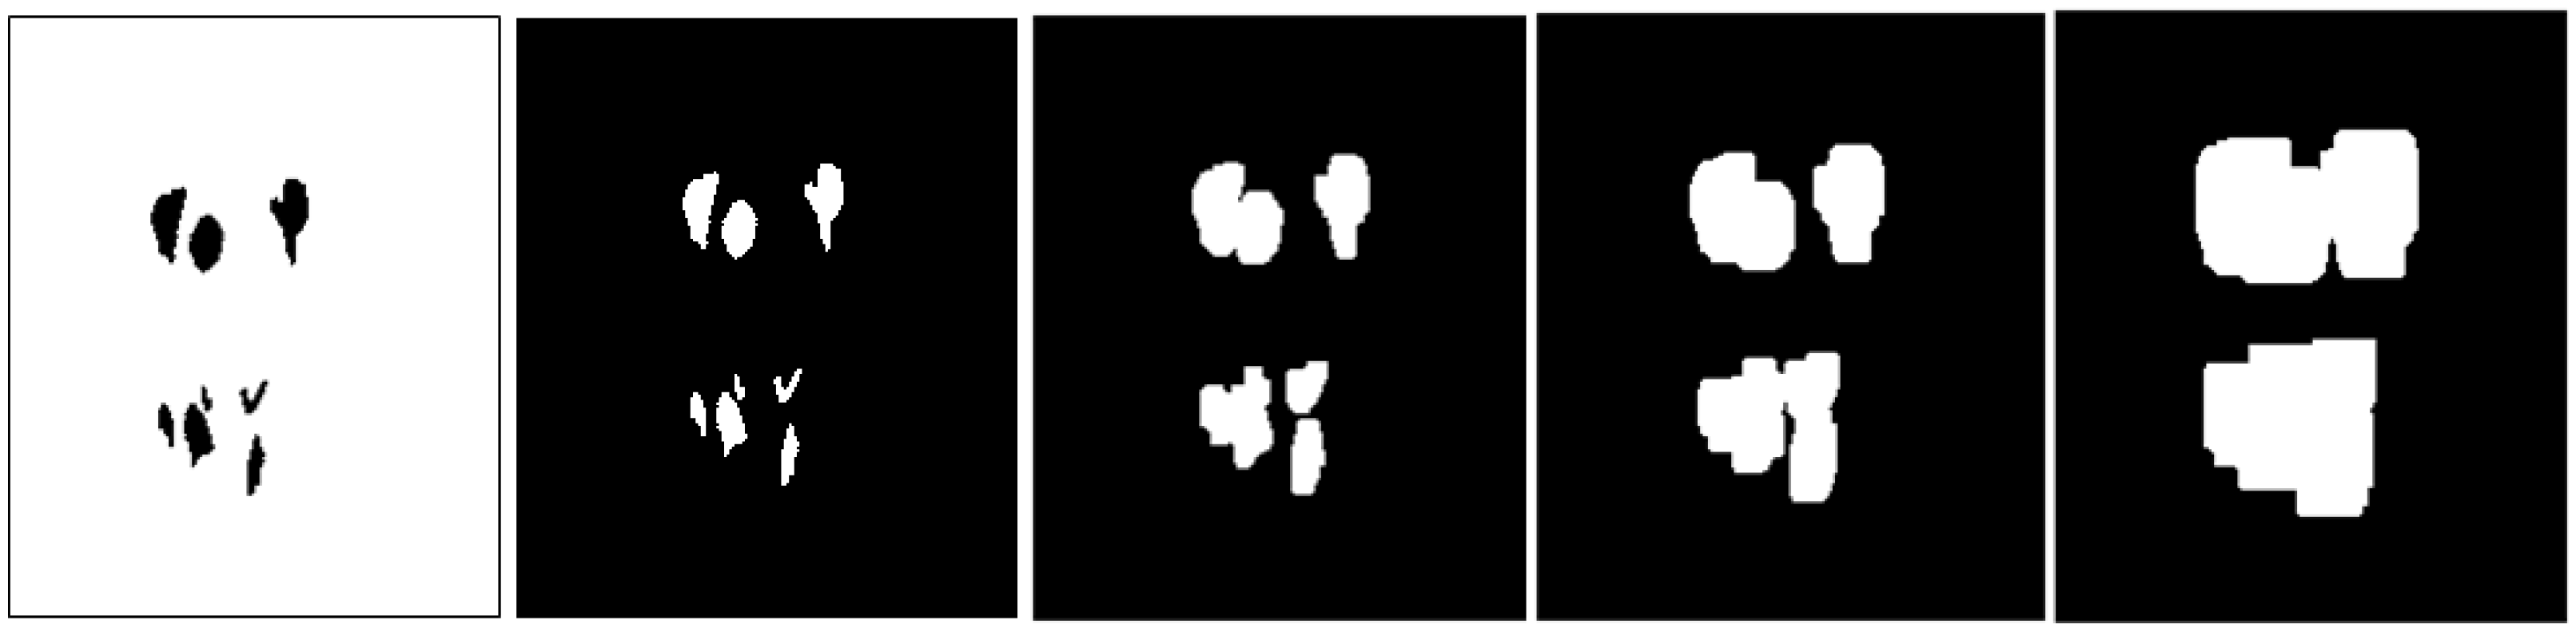

Appendix B.1. Multi-Level Distance Features